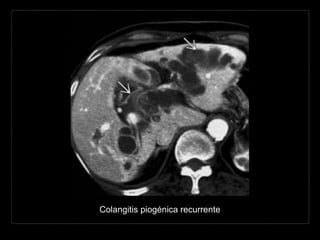

COLANGITIS PIOGÉNICA

RECURRENTE

Cálculos de pigmento

biliar intra- y

extrahepáticos en

pacientes e

inmigrantes del sureste

de Asia.

Colangitis oriental, colangiohepatitis oriental

Hallazgos por TC

• cálculos hiperdensos o isodensos al hígado

• + C

• dilatación biliar intra- y extrahepática*

• dilatación del colédoco

• disminución del calibre abrupta en “cabeza de flecha”

• abscesos hepáticos (20%)

• neumobilia*

• atrofia grasa de segmentos hepáticos.

Colangitis piogénica recurrente

COLANGITIS PIOGÉNICA RECURRENTE Cálculos depigmento biliar intra- y extrahepáticos en pacientes e inmigrantes del sureste de Asia. Colangitis oriental, colangiohepatitis oriental 1-4 cm

Hallazgos por TC •cálculos hiperdensos o isodensos al hígado • + C • dilatación biliar intra- y extrahepática* • dilatación del colédoco • disminución del calibre abrupta en “cabeza de flecha” • abscesos hepáticos (20%) • neumobilia* • atrofia grasa de segmentos hepáticos.